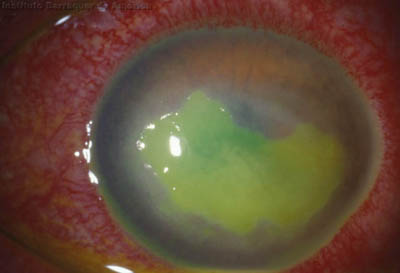

El cuadro clínico inicial progresa, aparecen infiltrados estromales anteriores focales o difusos, edema circunscrito y a veces perineuritis

En su evolución se observará aumento del edema, aparición de un anillo inmunológico (Wessely), agrandamiento y coalescencia de los infiltrados que progresan hacia la formación de un absceso, queratolisis superficial, adelgazamiento y perforación corneal.

Anillo inmunológico de Wessely

- Es la expresión de la interacción de los antígenos extraños con los anticuerpos que se difunden desde los vasos limbares hacia el estroma.

- Representa la formación de un complejo inmune que activa el sistema del complemento.

- El anillo de Wessely contiene principalmente neutrófilos

Inicio de síntomas 60 días - 12 meses curación

La vascularización y el hipopion son poco frecuentes en los estadios tempranos de la queratitis. Con el tiempo, en los estados avanzados de invasión estromal, aparecen vasos estromales

Cuando la invasión por Acanthamoebas es estromal, la respuesta celular tiene como consecuencia, que la abscesificación del estroma continuará aumentando a pesar del tratamiento….. y su resolución es lenta.

Evolución Complicada

Início síntomas 60 dias - No PL